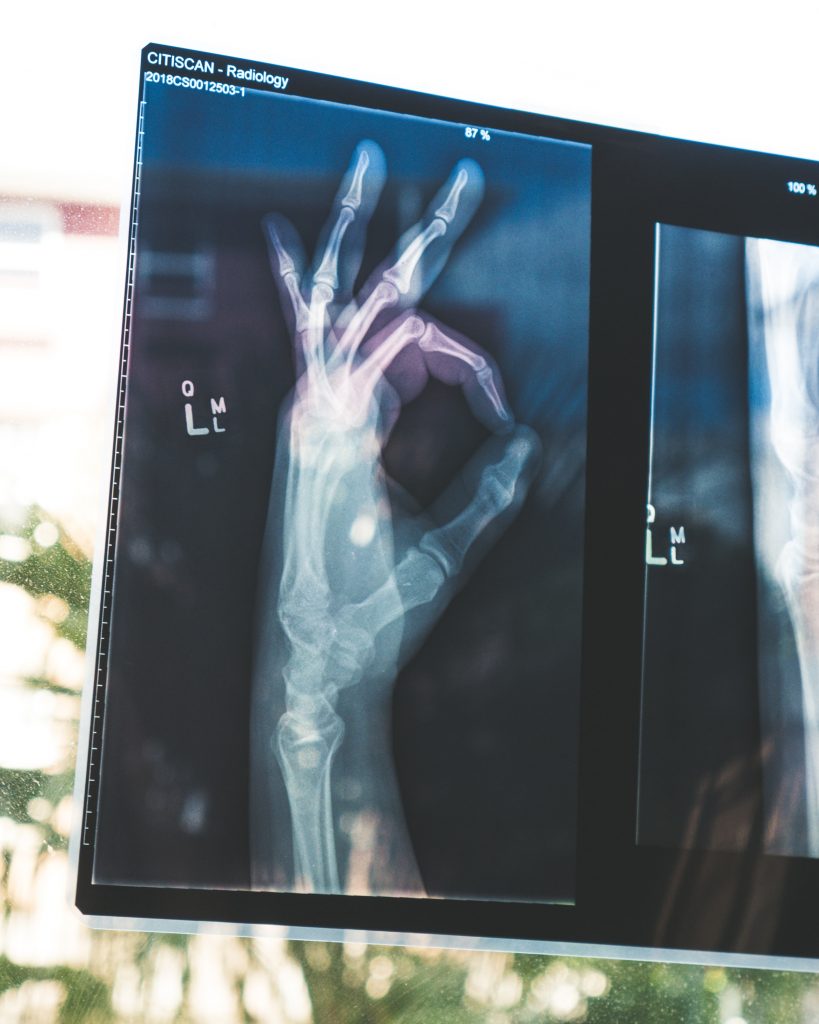

Santé des os et alimentation

On pense généralement trop tard à la bonne santé de nos os, en vieillissant avec le risque d’ostéoporose, alors qu’elle se travaille à tout âge.

Notre squelette connait un renouvellement permanent tout au long de la vie. Il est remplacé environs tous les dix ans. Ce processus est le cycle de remodelage osseux. La santé des os dépend donc de l’équilibre entre la fabrication et la résorption osseuse.